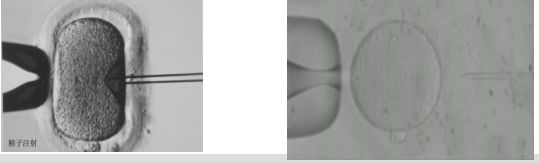

图2. 单精子注射受精